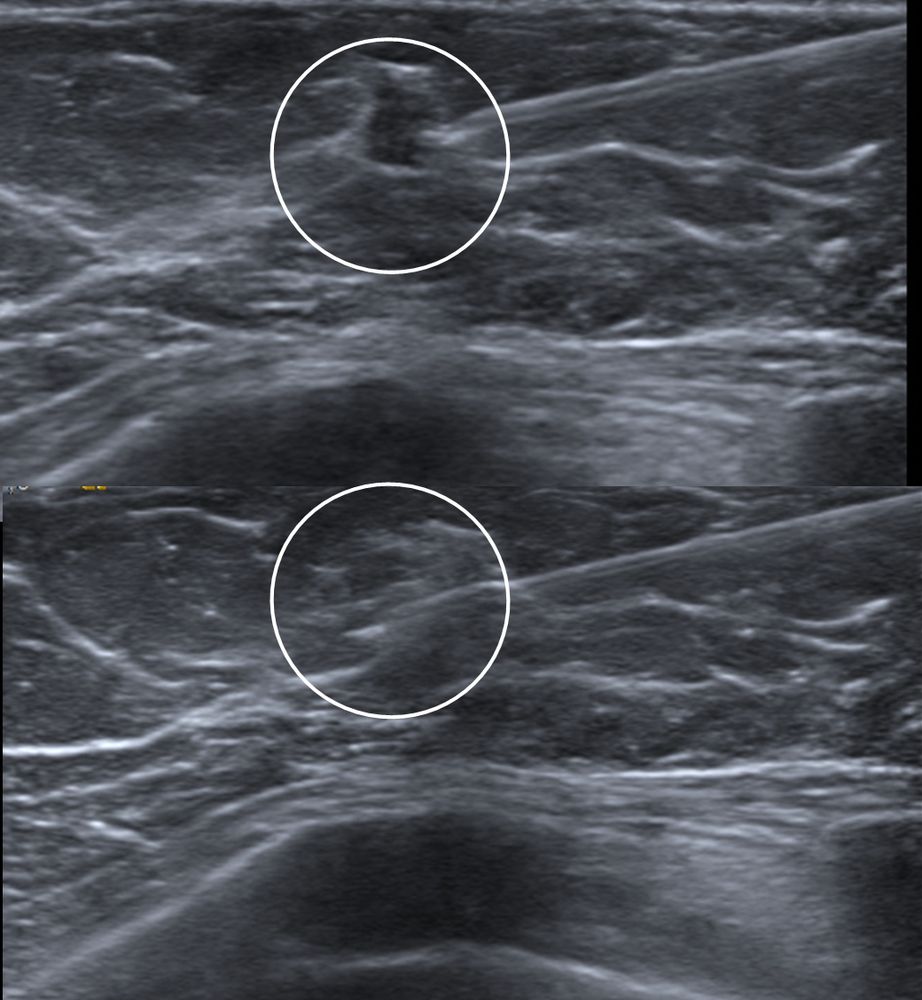

Σε περίπτωση που απαιτείται η χειρουργική αφαίρεση ενός ευρήματος που δε ψηλαφάται από το χειρουργό, τότε γίνεται η τοποθέτηση αγκίστρου σήμανσης (hook) λίγο πριν το χειρουργείο. Το άγκιστρο έχει σκοπό να καθοδηγήσει το χειρουργό για την αφαίρεση του σωστού τμήματος του μαστού, ώστε να αφαιρεθεί με ασφάλεια η ύποπτη βλάβη χωρίς να επηρεασθεί η αισθητική εικόνα του μαστού, πράγμα πολύ σπουδαίο ειδικά σε νέες γυναίκες και σε γυναίκες με μικρό μαστό.